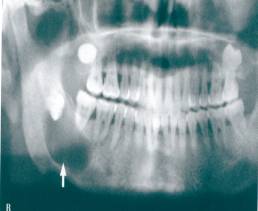

主要包括牙槽外科手术(含各种牙齿的拔除、牙槽骨修整手术、牙种植术等),口腔颌面部炎症及颞下颌关节疾病的诊断与治疗,口腔颌面部创伤(含颌面部软组织创伤及骨折)的诊断与治疗,口腔颌面部及唾液腺(腮腺、颌下腺、舌下腺)肿瘤的诊断与治疗等。